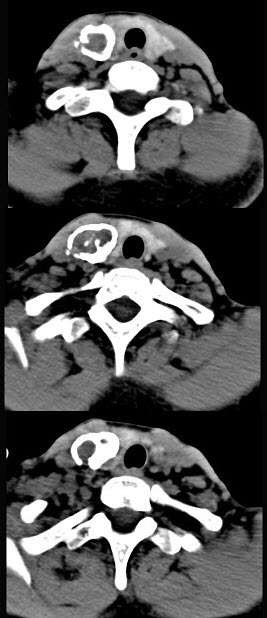

50岁女性患者,体检发现右侧甲状腺有较硬结节,CT扫描如图所示,请选择正确的描述和答案()。

A、右侧甲状腺内见稍低密度影,周边围以环形致密钙化影

B、肿块影与周围结构分界清楚

C、考虑为结节性甲状腺肿

D、考虑为甲状腺癌

E、考虑为甲状腺腺瘤钙化

A,B,E